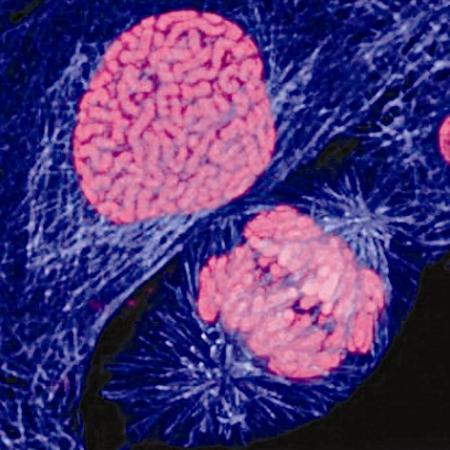

正在分裂的乳腺癌细胞